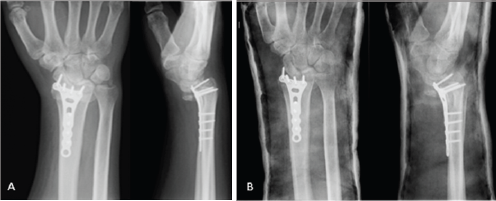

A 48 year-old male, caucasian, policeman, right handed, attended the emergency service due to right wrist pain and functional impotence. Five weeks earlier he had suffered a road accident resulting in a fracture of the distal right radius (AO subtype 23-B3) (Figure 1) and a tibial plafond fracture. At a foreign hospital that received him, he was submitted to radius osteosynthesis with an anatomic volar distal radius plate and in the lower right limb a temporary joint-bridging external fixation was placed during 1 week, and was posteriorly substituted by screws and plate fixation in the tibia and fibula. The wrist cast was removed 4 weeks after surgery in a private hospital in our country. After this episode he began to feel pain, without any history of associated trauma. He had no other previous history of interest. The physical examination revealed a "dinner fork” deformity, with a volar translation of the carpus. The skin was intact. There was no neurovascular deficit. Imaging showed a Dumontier type II volar radiocarpal dislocation (Figure 2A). At the emergency department we conducted closed reduction through traction after infiltration of a local intra- articular anesthetic, without success nevertheless (Figure 2B), so we decided to proceed to surgical treatment. Intraoperatively, through a volar approach of the radius, a bone fragment distal to the plate was visible. A dorsal approach was needed to reduce the dislocation. A radiocarpal fixation with three Kirschner wires was performed, two of them fixing the volar fragment of the distal radius, and one stabilizing the radiocarpal joint. One screw of the plate was removed due to its' intraarticular location. The distal radioulnar joint was evaluated under dynamic fluoroscopy and was apparently stable. Immediate postoperative radiographs confirmed a concentric reduction and stable fixation of the radiocarpal joint (Figure 3). Postoperatively, the patient was placed in an arm cast with free elbow and metacarpophalangeal (MP) joints. There were no perioperative complications. The immobilization and the kirschner wires were maintained for 7 weeks. After removing the cast and the kirschner wires, the patient presented flexion of 20°and extension of 15°, which improved up to flexion 30° and extension 60°, supination 60°, with preserved pronation, 24 months after the trauma. At this time, the patient reports no pain, feeling of instability or signs of nerve compression. The DASH disability score result was 3,1 and the Mayo Wrist Score was 93. The radiograph control did not show any relevant alteration (Figure 4).

Figure 2: (A) Posteroanterior (PA) and lateral radiographs of the right wrist show volar dislocation of the carpus at our emergency department (B) Postreduction attempted failed PA and lateral radiographs of the right wrist.